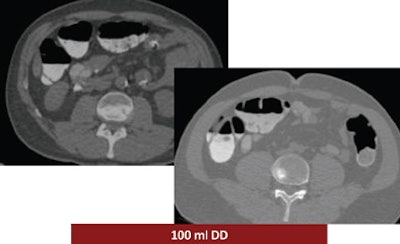

The study looked at three groups of 30 patients who underwent virtual colonoscopy after a same-day bowel preparation. Group 1 ingested 200 mL of undiluted DD the day of the exam, group 2 drank 100 mL of the agent the day of the exam, and group 3 ingested a low-dose polyethylene glycol (PEG) formula (macrogol) the two days before the exam, followed by 100 mL of DD the day of the exam.

Group 1 had the best-quality results, with well-marked colonic mucosa but significant residual fluid. The use of 100 mL DD combined with low-dose polyethylene glycol over two days may have improved fecal tagging by softening the stool before the ingestion of the iodinated agent. In addition, no side effects were reported among the patients who ingested the PEG preparation for two days before the exam (group 3), Ferrari said.

| Above, the use of 200 mL DD in group 1 yielded the highest quality scores. While the colonic mucosa was well marked, significant volumes of fluid remained in the colon, similar to the 100 mL DD preparation (group 2, below). The use of 100 mL combined with low-dose polyethylene glycol over two days (bottom image) may have improved fecal tagging by softening the stool before the ingestion of DD. |